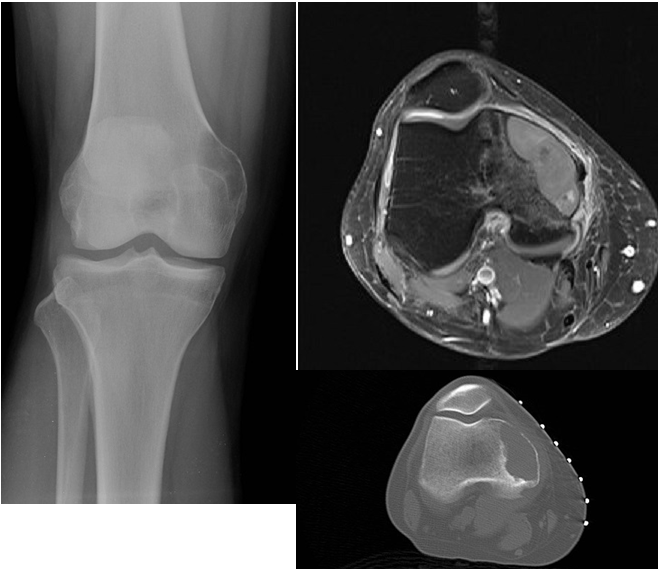

Learning Objectives: At the conclusion of the general orthopedic self-assessment exam physician assistants should be familiar with radiographic characteristics of benign and malignant bone tumors, be able to identify common benign bone tumors including enchondroma, unicameral bone cyst, nonossifying fibroma, osteoid osteoma, aneurismal bone cyst, giant cell tumor, and osteochondroma, be able to identify common malignant bone tumors including osteosarcoma, chondrosarcoma, and Ewing’s sarcoma, and be able to identify and understand treatment of pathological fractures from metastatic disease.